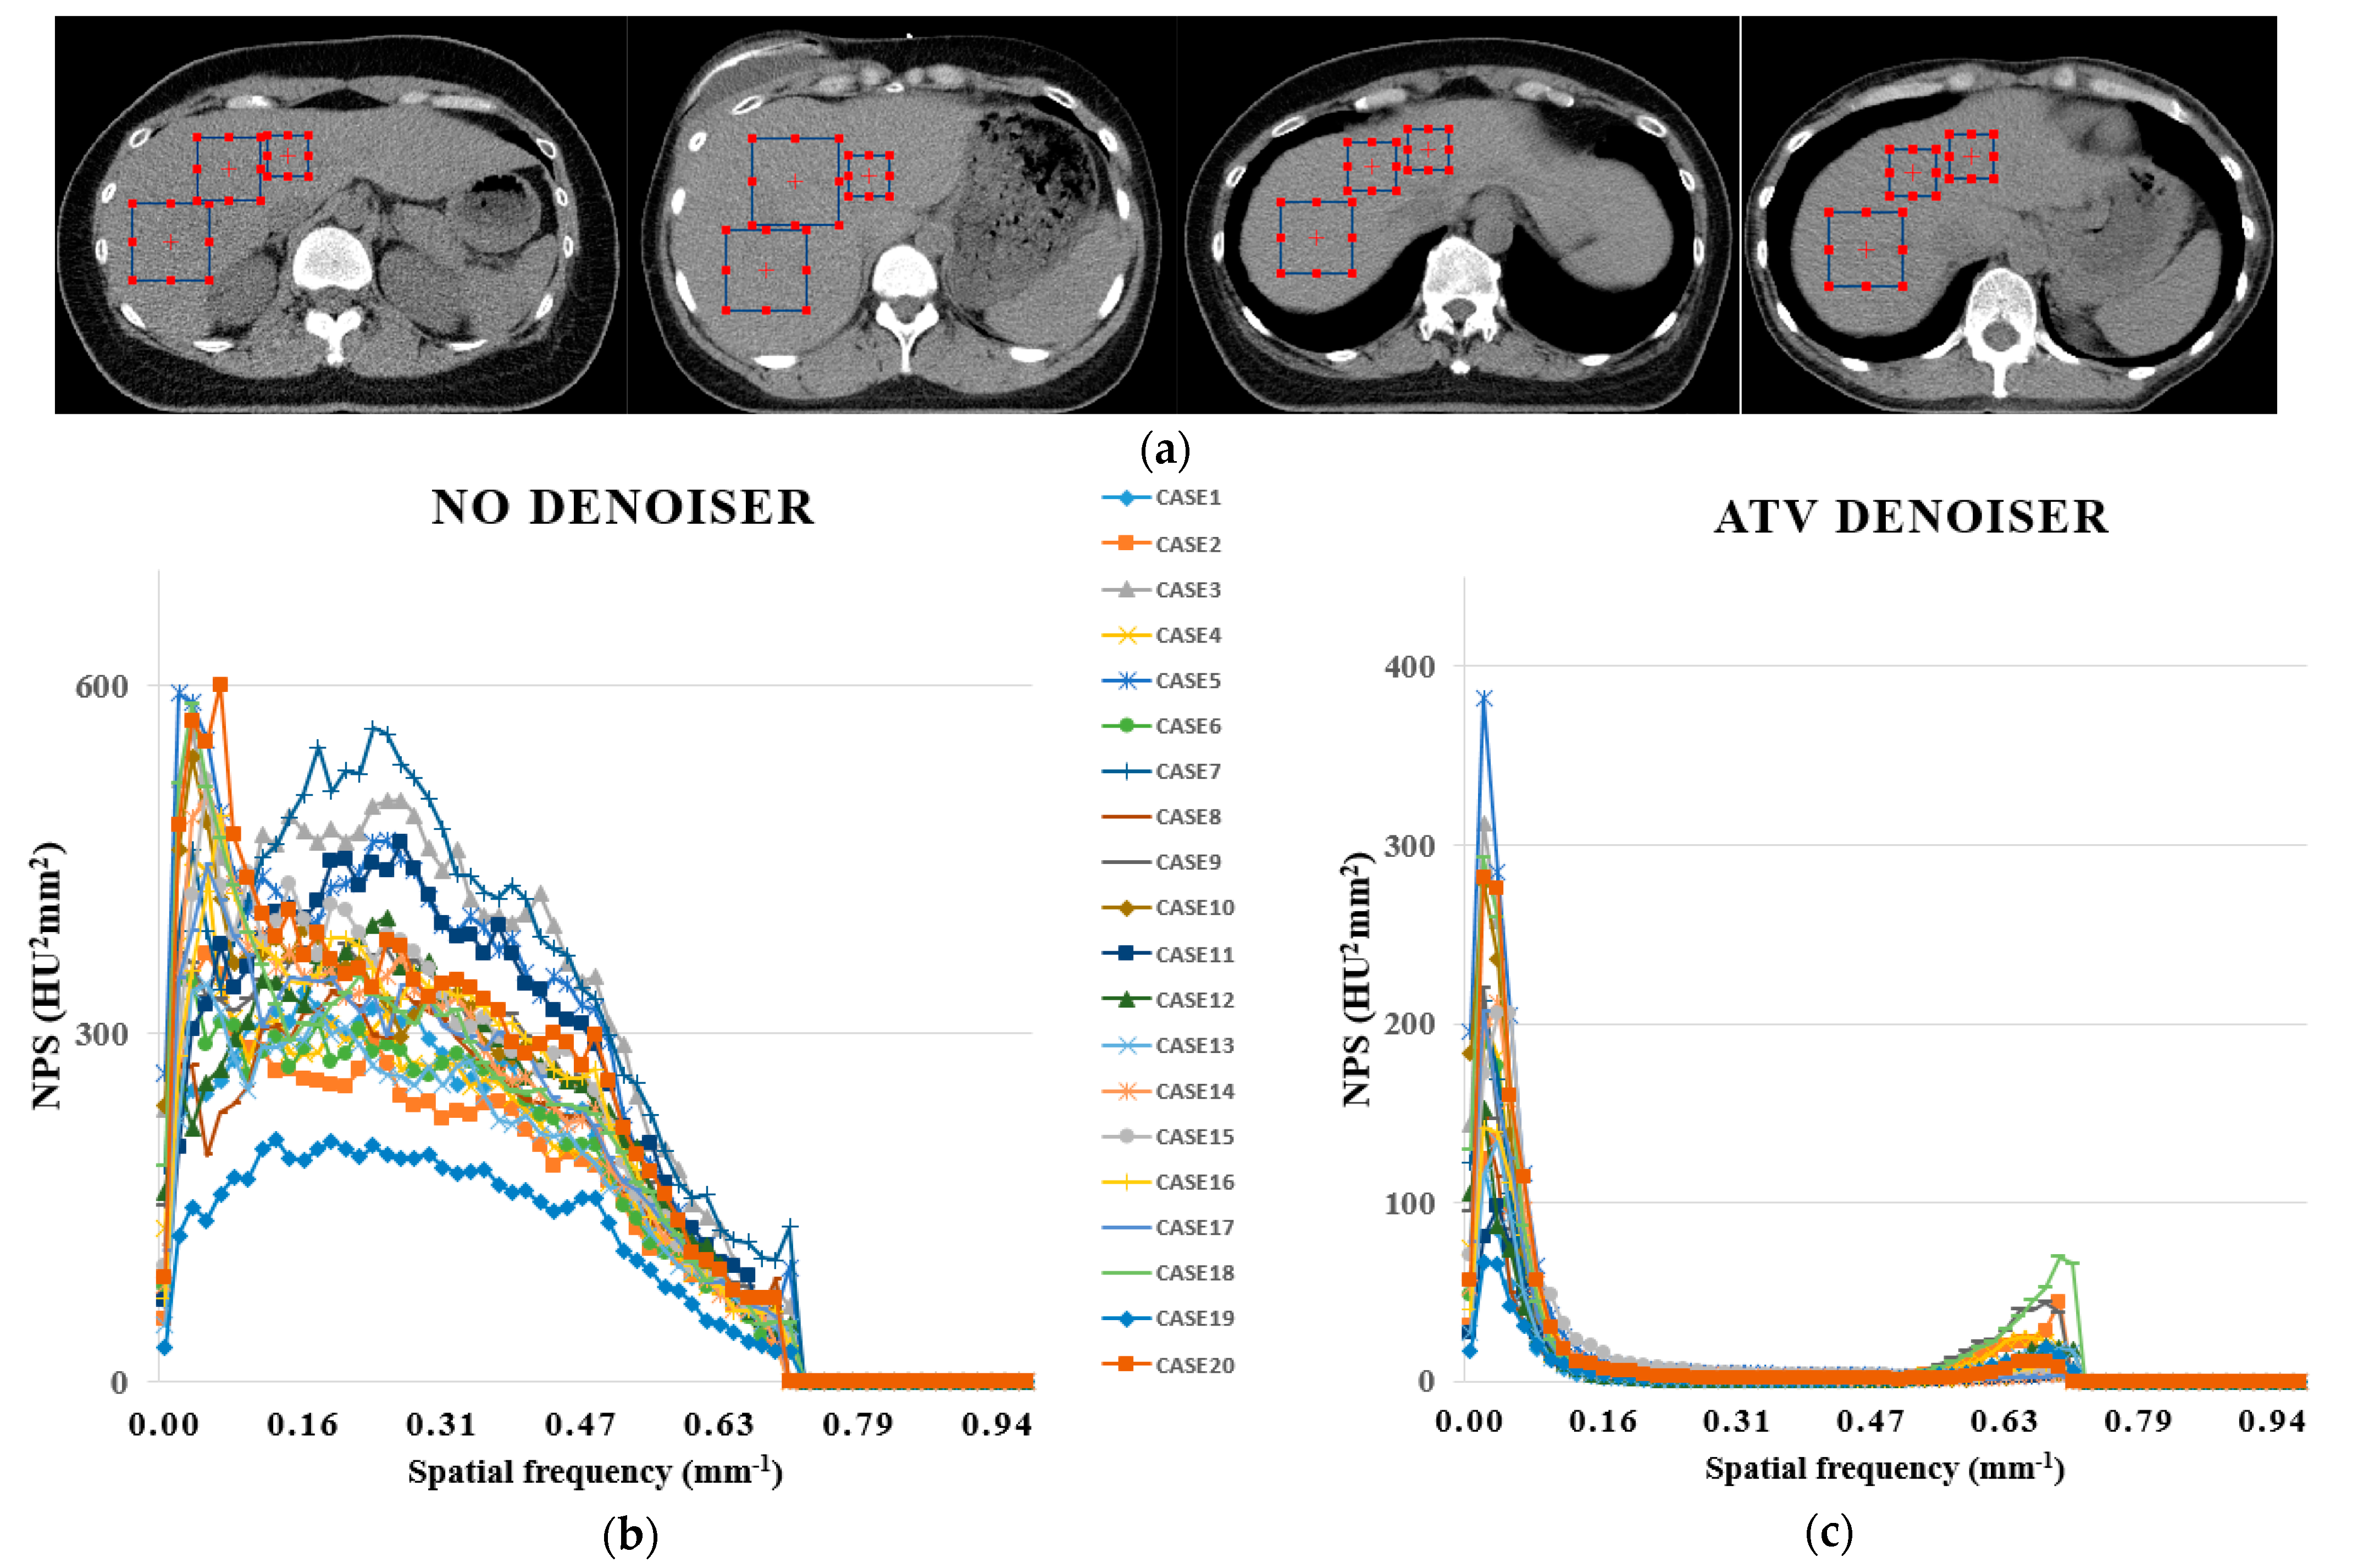

2.3. Anisotropic Total Variation Denoiser-Based Auto-Segmentation

2.4. Quantitative Analysis